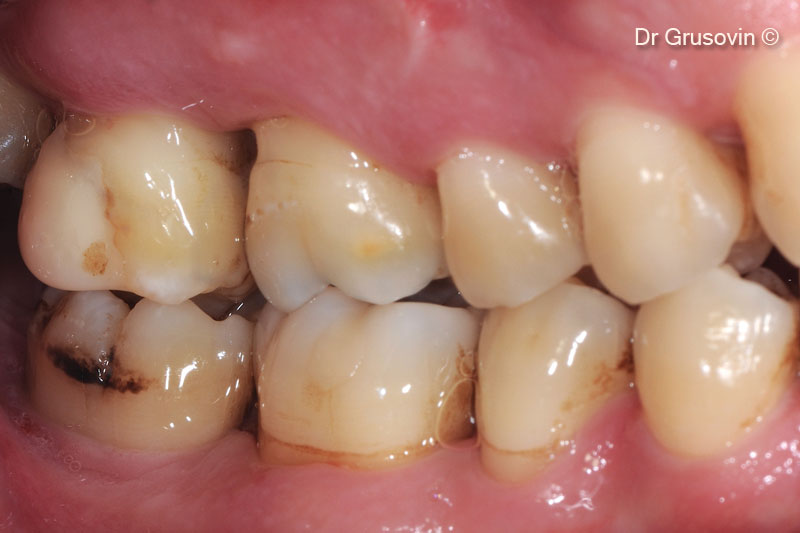

1. Healthy patient, non smoker intraoral clinical view buccal

2. #16 vital, furcation III involvement vestibular distal